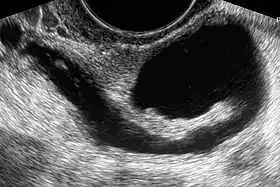

Sonohysterography using a balloon catheter (seen in the middle of the image)

Sonohysterography is a specialized procedure by which fluid, usually sterile saline (then called saline infusion sonography or SIS), is instilled into the uterine cavity, and gynecologic sonography performed at the same time. A review in 2015 came to the conclusion that SIS is highly sensitive in the detection of intrauterine abnormalities in subfertile women, comparable to hysteroscopy. SIS is highly sensitive and specific test in the diagnosis of uterine polyps, submucous uterine fibroids, uterine anomalies and intrauterine adhesions (as part of Asherman's syndrome), and can be used as a screening tool for subfertile women prior to IVF treatment.[4]